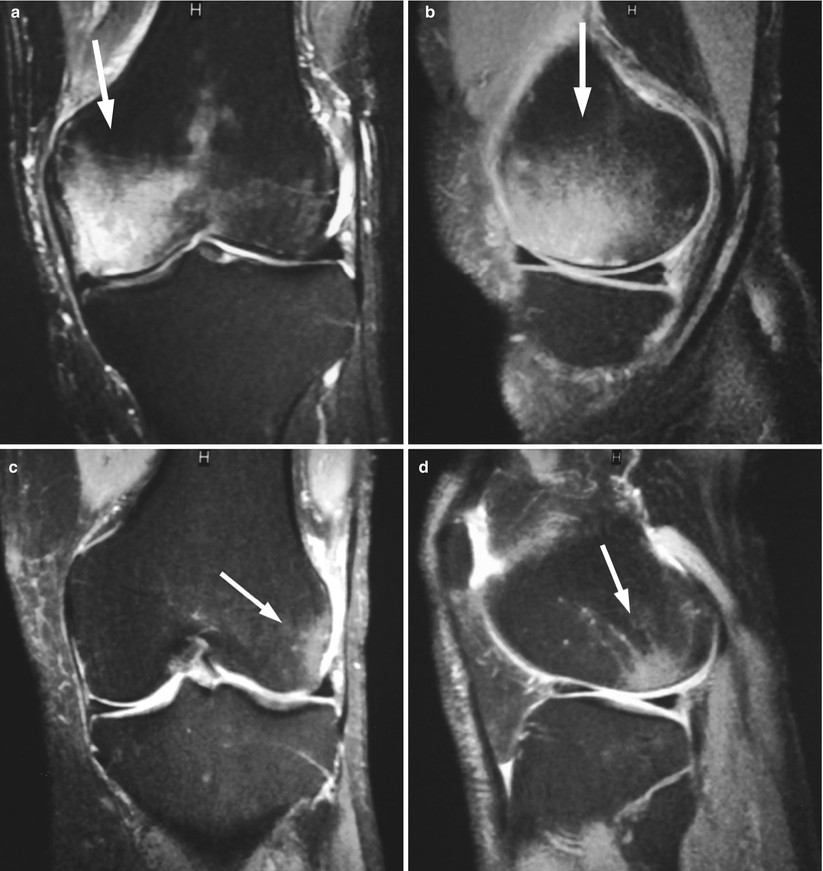

骨挫傷(Bone Bruise)或骨髓水腫(Bone Marrow Edema, BME),就是這棟建築在受到外力撞擊或長期壓力後,鋼筋出現了微小的裂痕,但建築主體尚未倒塌(骨折)。這種微觀層級的細微骨折,會導致骨髓內部出血、發炎、水腫,產生深層的疼痛 。

這種「骨內傷」在X光下常常看不出來,需要透過**核磁共振(MRI)**才能清楚看見骨髓內部的發炎訊號。

(出自: https://radiologykey.com/bone-marrow-edema-pattern/)